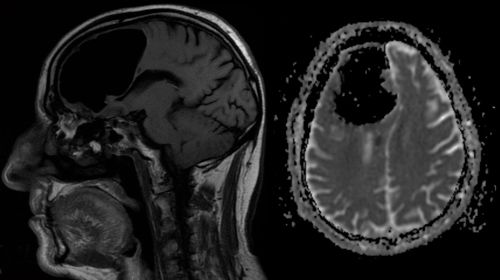

ЧИНОВНИК БЕЗ МОЗГА. В июле 2007 года в медицинском научном журнале «Lancet» была опубликована небольшая статья «Мозг чиновника». В ней рассказывалось о поразительном случае гидроцефалии у одного 44-летнего французского государственного служащего. Однажды этот человек обратился в госпиталь Марселя с жалобами на слабость своей левой ноги, однако, когда ему сделали томографию мозга, то увидевшие снимки врачи были шокированы.

Оказалось, что желудочки мозга этого клерка были так расширены, что занимали практически всю полость черепа. Тем не менее, хотя почти три четверти головного мозга отсутствовали, этот человек жил вполне нормальной жизнью: работа, семья, дети.

Никаких особых проблем с психикой, как ни странно, он не испытывал. Хотя был несколько глуповат – его коэффициент интеллекта (ІQ) составлял всего 75 пунктов (при норме от 80 до 114). Если бы у него не возникли проблемы с ногой, то, возможно, никто бы и не узнал, что в его голове большую часть «жилой площади» занимает не мозг, а спинномозговая жидкость.